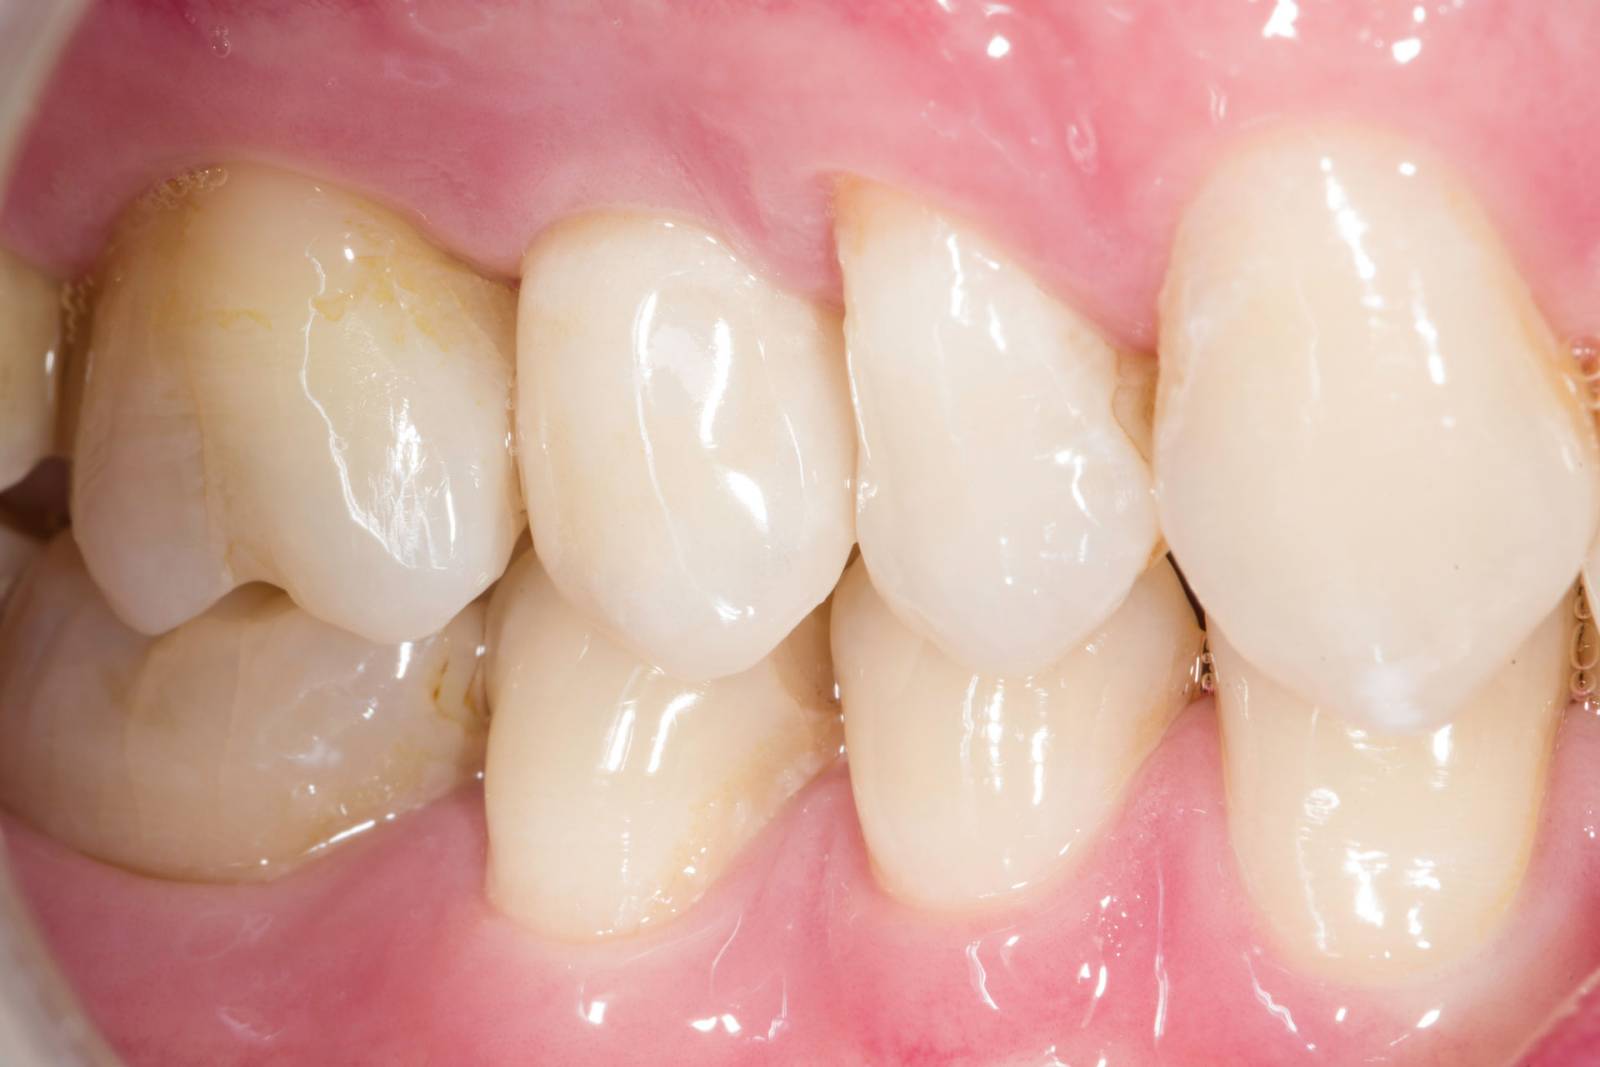

Before: Fractured metal-ceramic crown on tooth 14, which had previously been treated endodontically.

After: Translucent full zirconia crown for an esthetic result with maximum resistance and retention shape.